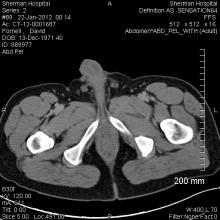

Radiotherapy using protons can deliver more accurate treatment to a tumor while reducing the dose to surrounding tissue. However, in mobile organs such as the lung, precise targeting of the dose is difficult. Now researchers have succeeded in making a model of breathing movement that allows for the precise measurement of narrow beams to a dummy tumor by simulating the motion and physical properties of the chest anatomy in a model, which was presented at the 3rd European Society for Radiotherapy and Oncology (ESTRO) Forum in Barcelona, Spain.